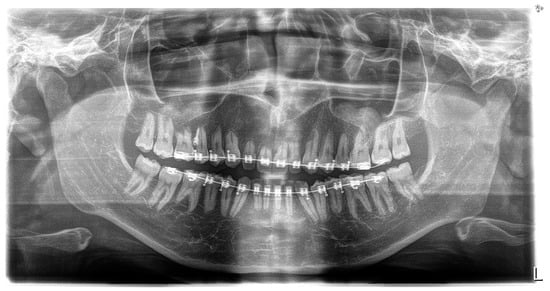

Figure 2. Pre-treatment intraoral photos (the upper line—right, mid, and left occlusion, the lower line—upper arch and lower arch forms).

A short periodontal examination, performed in our clinic in this kind of patient was performed. No need for further specialist examination was reported. The periodontal biotype and oral hygiene were both established as correct (Figure 2).

Clinical intraoral examination, performed in November of 2018, revealed class II subdivision 2, with lower midline deviation to the right of the upper midline. The clinicians also observed dental crossbite on a single tooth, 17, deep overbite, retrusion of the upper incisors, and slight spacing in the upper arch.